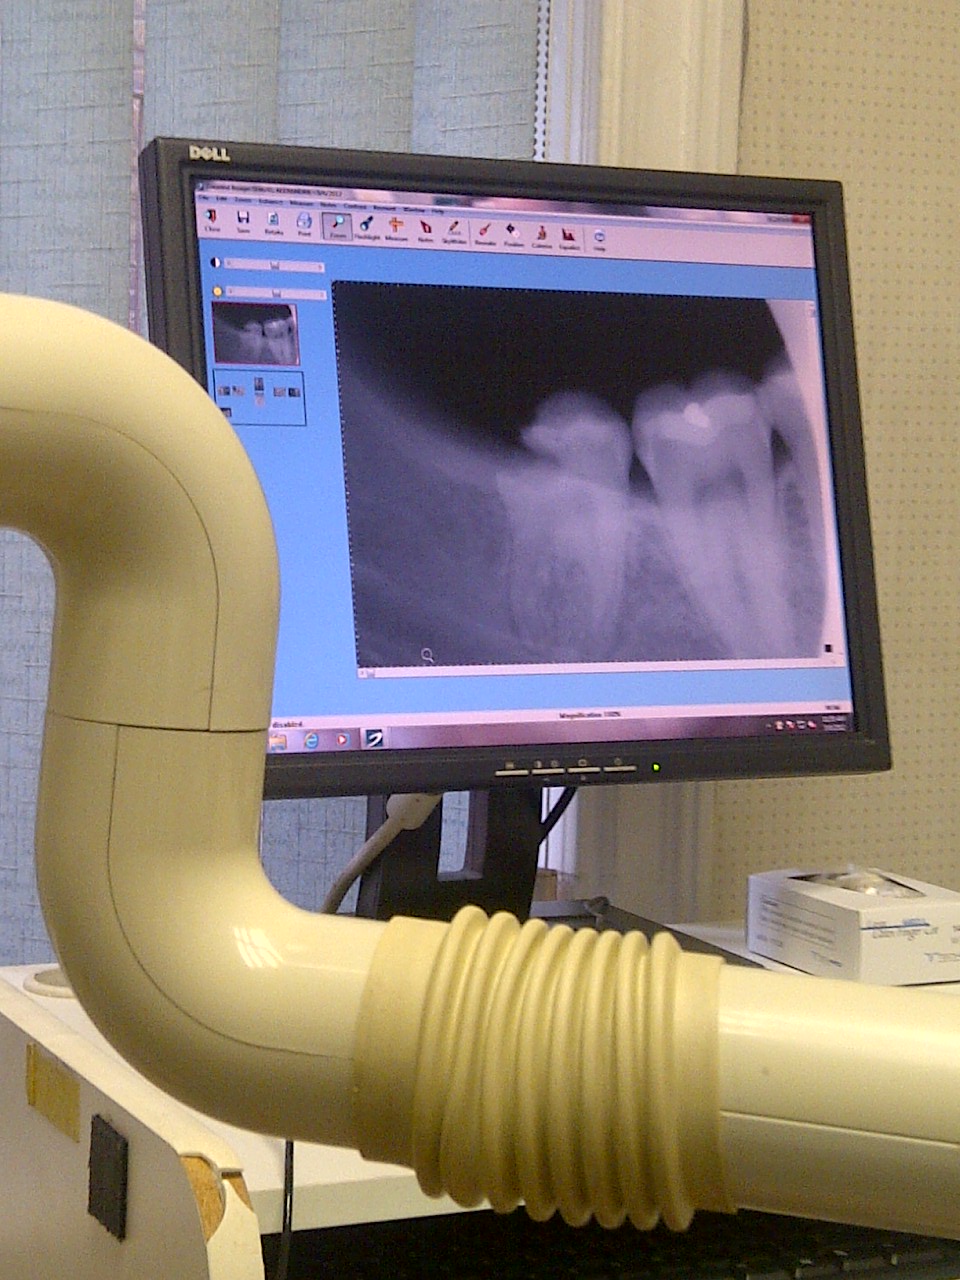

…and yes I snagged a pic of the xray panel. Bad news bears right?